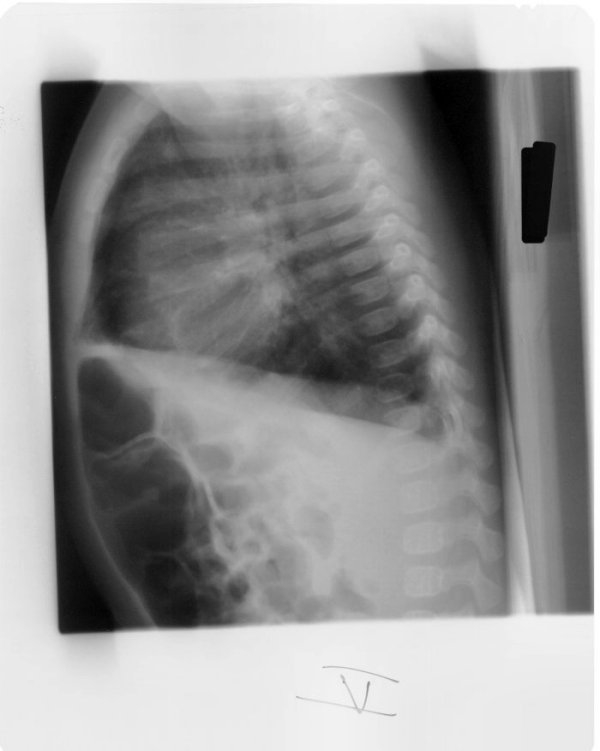

What is going on in this infant’s radiograph?

There is hyperinflation and increased perivascular markings. It can be fairly subtle, the perivascular markings are the biggets tell. Sometimes complete RUL collapse is observed.

On the lateral radiograph associated with this case you can better appreciate the hyperinflation via the flattening of the diaphragm.

In the right clinical context, this is suggestive of bronchiolitis, particularly RSV.